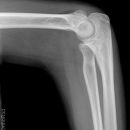

Fat Pad Sign

nicht dislozierte Radiusköpfchenfraktur

Ellenbogenluxation